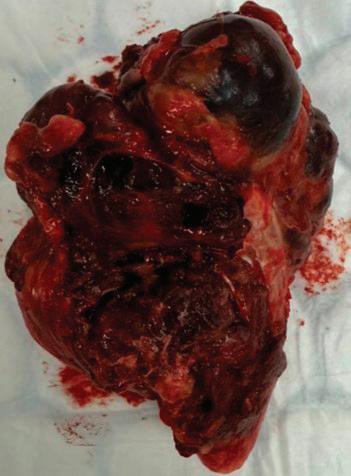

За по-ясна илюстрация на диагностичните и хирургичните предизвикателства при форма -

ции на шията с неизвестно първично огнище, представяме серия от пет клинични случая, подбрани от практиката на клиника по УНГ болести, УМБАЛ „Каспела“.

Всеки от тях демонстрира различен аспект на проблема – от типични плоскоклетъчни метастази до редки хистологични варианти и дори случаи, при които първичното огнище остава недостъпно за идентификация.

чество

Случай

подготовка на пациента за кардиохирургична оперативна интервенция в обем 3 аорто-коронарни байпаса. От проведената КТ се установява хетероденсна формация на ниво II шиен лимфен колектор, с размери 13/18 мм. От анамнезата няма данни за болка, дисфагия, диспнея или дисфония. При наблюдение в следоперативния период се отчита постепенно нарастване на размера на формацията.

Поради динамика в локалния статус пациентът се насочва за консултация и последващо лечение в УНГ клиника, където от проведените образни изследвания (КТ, УЗД) се на -

блюдава хетероденсна мекотъканна формация с размери 25/28 мм, наличие на кистични

зони в обема й и лифмни възли по съседство.

След ексцизионна биопсия, хистологията до -

казва масивна метастаза от умерено диференциран плоскоклетъчен карцином. Насоченото

чен източник.

Случай 3: Метастатична шийна

жена, А.С., постъпва с плътна, неболезнена, прогресивно нарастваща формация на шията вдясно, ниво III, която причинява и лекостепенна дисфагия. Липсват оплаквания от страна на горните дихателни пътища, температура или нощно изпотяване. Ехографското изследване показва хомо

контролна КТ, с данни за лимфогенна шийна диссеминация двустрнно. Извършена радикална

шийна лимфна дисекция двустранно, с хистологичен резултат метастази от умерено диференциран невроговяващ плоскоклетъчен карцином. Три месеца по-късно при проведен контролен ПЕТ/КТ данни за зави -

шена метаболитна активност на ляв шиен

лимфен възел ниво II. Предприе се ексцизия

на същия с хистологичен резултат масив -

на метастаза от невроговяващ плоскоклетъчен карцином. Три месеца по-късно проведен повторен контролен ПЕТ/КТ, от който са